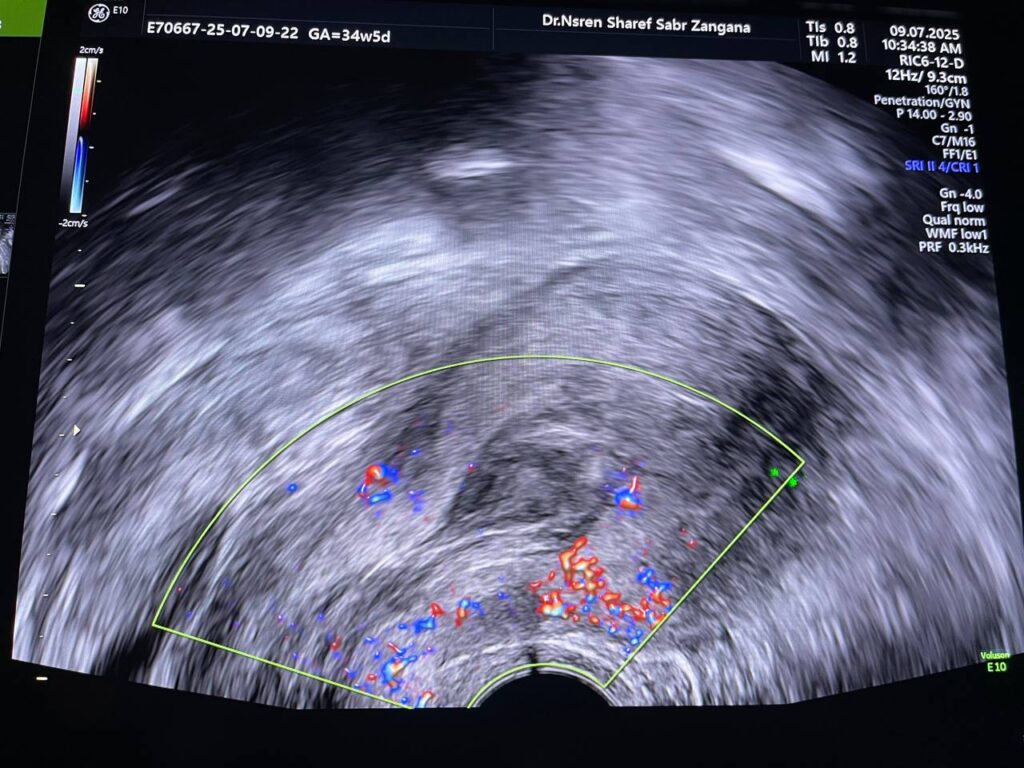

Bulky size, A/V uterus,  endometrial lining thickness 22mm, the cavity occupied by heterogenous avascular lesion 42x16mm , mostly blood clots? in addition to presence of few cysts with instinct  left anterior upper part of the endo myometrial junctional zone , in area size about 11.5x9mm, mostly remains of hydatiform wall  , please for further study   , no fibroid

This patient has high BHCG level , with History of H Mole on march 2025